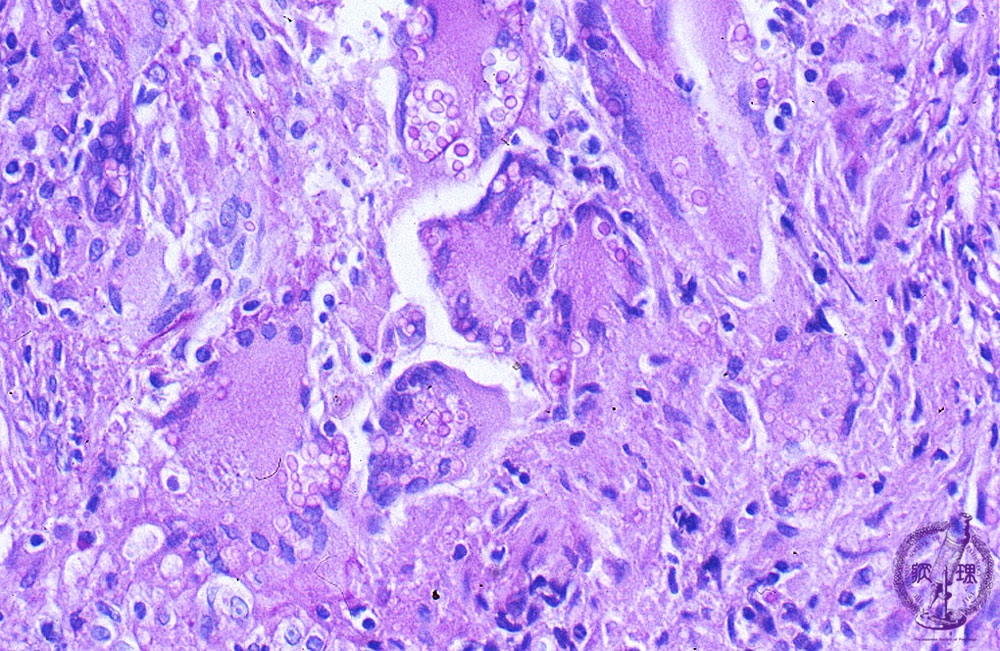

- ★(9)Fungal pneumonia (Cryptococcosis)

Microscopic view (PAS stain, high power view): The mucopolysaccharide membrane of Cryptococcus is red-violet on PAS stain. Unlike to aspergillus, Cryptococcus is a round, yeast-like fungus.